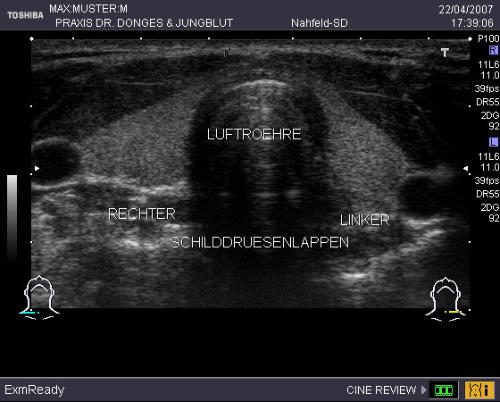

Schilddrüse Ihre Schilddrüse bildet Hormone, die für den Stoffwechsel von großer Bedeutung sind. Sie benötigt hierfür eine genügende Jodzufuhr mit dem Trinkwasser und der Nahrung. Trotz aller Anstrengungen ist die Jodversorgung in Deutschland noch nicht ausreichend, so dass aktuell immer noch jeder dritte Erwachsene (!) eine vergrößerte oder knotig veränderte Schilddrüse hat. Durch Früherkennung und Behandlung lassen sich spätere Operationen vermeiden. Deshalb bieten wir Ihnen einen Vorsorgetest an, der neben dem Abtasten eine Ultraschall- untersuchung der Schilddrüse und einen Laborwert (TSH) beinhaltet. Hiermit können wir das Organ exakt in Größe, Knotenbildung und Funktion beurteilen. Der Vorsorgetest ist keine Krankenkassenleistung.